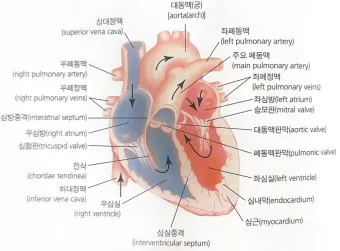

1. 심장 관련 원인

- 부정맥: 정상 심박수 범위 60-100회/분 이탈

- 심장 판막 이상: 증상 발현 시 심박수 변동 20% 이상

- 빈맥증: 휴식 시에도 심박수 100회/분 이상

- 서맥증: 심박수 60회/분 이하로 저하